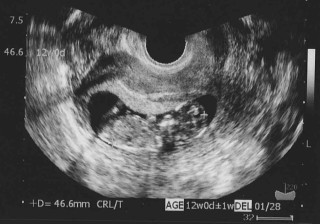

9wから倍以上の大きさ、46.6mmになってて、 エコー画面を見た瞬間思わず「でかっ」と言ってしまいました。 角度によって頭蓋骨の目鼻口も見えました。 ちっちゃいドクロちゃんですが、気持ち悪いとかではなく とっても可愛いと思えました。